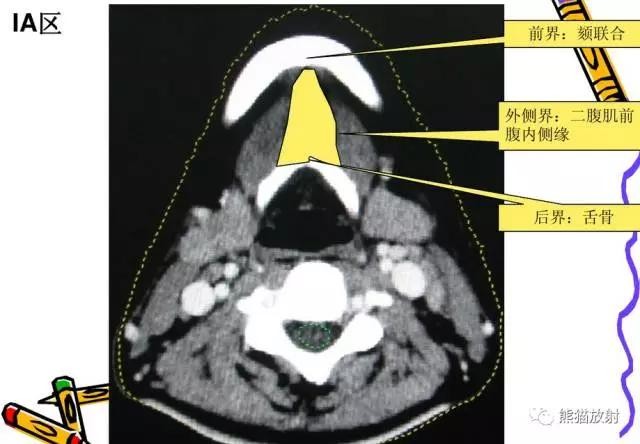

I区:颏下及颌下淋巴结

舌骨上水平CT增强图像

横白线在两侧颌下腺后缘。

线以前为I区淋巴结,线后为II区淋巴结。在颈内静脉附近为IIA区,颈内静脉后面不接近静脉的淋巴结为IIB区。